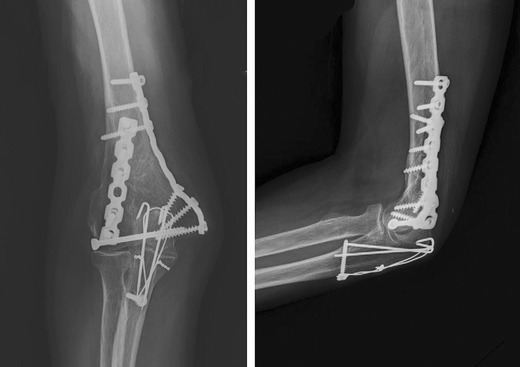

Open reduction and internal fixation has become the treatment of choice for fractures of the distal humerus [42–44]. Achieving rigid internal fixation and anatomical reconstruction is essential for allowing early ROM exercise, adequate bone healing, and avoiding future cartilage degeneration [45•]. Biomechanical studies could demonstrate the advantages of double plating over single plating in proximal and intraarticular fractures of the distal humerus, providing the necessary stability and rigidity [17, 46–48]. The standard fixation that has been used by most surgeons is double plating with the two plates perpendicular to each other [15, 45•, 49]. Nevertheless, cadaver studies described already in 1994 equivalent rigidity of plates placed parallel or perpendicular to each other (Figs. 1 and 2) [50]. Korner et al. compared the 90° offset method to plates that are being placed both dorsally in sawbone with superior outcome of the perpendicularly placed group [42]. Further biomechanical investigations that differentiated between fracture patterns with or without bone loss, suggest that in cases with a gap in between fragments, the 180° plate configuration shows the highest rigidity, followed by the perpendicular and a dorsal arrangement. On the other hand, no significant differences in rigidity between the three fixation configurations could be found in the case of no gap in between the bone fragments [51].

Fig. 1.

ORIF distal humerus, parallel plating

Fig. 2.

ORIF distal humerus, perpendicular plating. Both figures reprinted with permission from: SJ Shin et al. [52]

In clinical investigations, Shin et al. indicated an increase of non-union in the perpendicular plating group but no significant difference concerning the clinical outcome to the parallel plating group [52] whereas Lee at al. highlighted no statistically significant differences concerning the clinical outcome and union time between the two groups [45•]. It has still to be elucidated to which extent specific fracture patterns of the distal humerus could be correlated to one plating method. Perpendicular plating might be desirable for coronal shear fractures gaining additional stability in the coronal plane, whereas parallel plating might be preferred in fractures of the most distal part of the humerus giving the opportunity for additional distal screw fixation [45•].